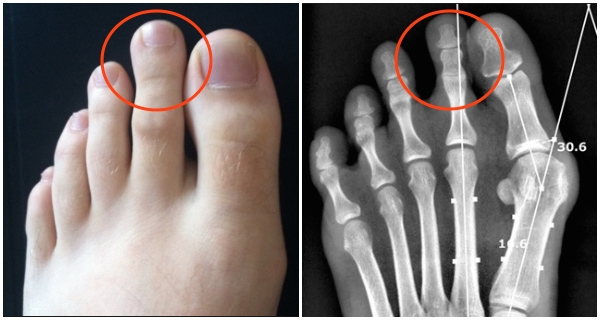

Bàn chân có ngón trỏ dài hơn ngón cái được gọi là "bàn chân Hy Lạp". Dưới góc độ y học, những người có bàn chân như vậy thường có nguy cơ mắc bệnh viêm tấy khớp xương ở kẽ ngón chân cái.

Khi ngón trỏ dài hơn những ngón còn lại trong bàn chân, thì khi chúng ta đứng hoặc đi bộ nó sẽ phải chịu áp lực nhiều hơn cả. Khi đó các ngón chân còn lại sẽ có xu hướng tiến sát lại gần nó hơn như một cách để chia sẻ bớt gánh nặng. Điều này khiến cho phần dây chằng ở bên ngoài mắt cá chân bị kéo giãn, dễ bị tổn thương. Dễ dẫn tới tình trạng viêm sưng, bầm tím, cơn đau cấp tính... khi chân bị gò bó nhiều.

Trong ảnh chụp X-quanh, khi ngón trỏ dài hơn thì phần xương ngón chân cái cũng bị ép và cong sát vào với nó.

Mặt khác việc ngón trỏ dài hơn các ngón cái khiến cho các nhánh thần kinh giữa xương bị chèn ép khiến các ngón chân bị đau nhức mỗi khi mang giày, nhất là giày cao gót trong thời gian dài.